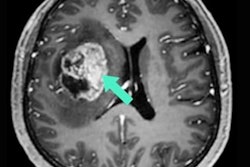

SubtleGAD uses AI to reduce necessary gadolinium dose during MR exams, and it can process images at 10% of typical doses, the company said. It is part of the company's portfolio of AI tools for radiology, which also includes SubtleMR and SubtlePET.

MRI images processed with Subtle's SubtleGAD algorithm at 10% of the original gadolinium dose. Image courtesy of Subtle Medical.SBIR is a U.S. government program coordinated by the Small Business Administration.